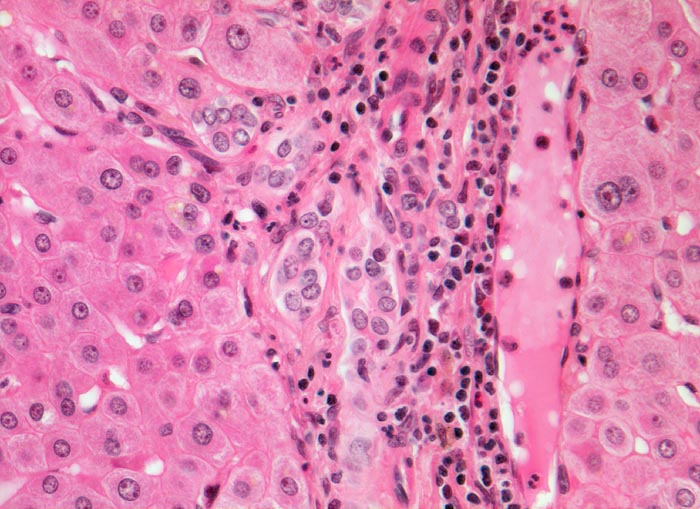

Leber bei mechanischem extrahepatischem Verschlussikterus

In der Zone 1 rund um das Portalfeld sind keine Galleablagerungen erkennbar. Das Portalfeld zeigt ein gemischtes Entzündungsinfiltrat. Am Rand des Portalfeldes proliferierte Ductuli umgeben von neutrophilen Granulozyten.

Patient mit Sklerenikterus seit 3 Wochen. Bekannte Cholezystolithiasis mit rechtsseitigen Oberbauchbeschwerden.

Bei kurzdauerndem extrahepatischem mechanischem Verschluss finden sich Galleablagerungen zunächst nur in der Zone 3. Das Portalfeld zeigt noch kein Ödem und keine Fibrose.